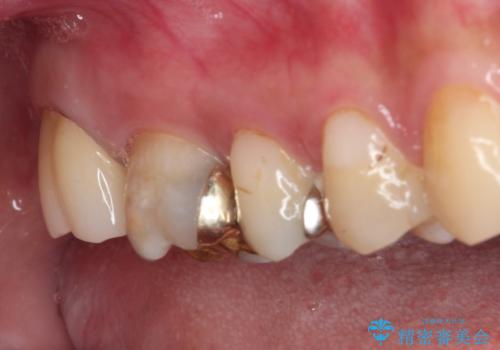

下顎の奥歯は強い痛みを感じており、既に歯髄に不可逆的な炎症が起きていると診断されたため、根管治療の後にセラミッククラウンにて補綴治療を行うこととしました。

下顎のむし歯は歯肉の中にまで及んでいたため、一部歯槽骨を削除し、歯肉縁上に健全歯質が位置するよう外科処置を併用しました。